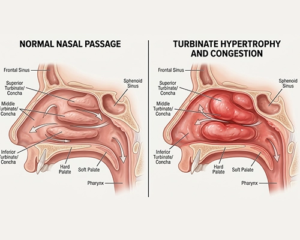

آیا شبها با گرفتگی بینی دستوپنجه نرم میکنید یا در طول روز برای تنفس راحت با مشکل مواجه هستید؟ بسیاری از افراد به اشتباه تصور میکنند علت اصلی گرفتگی مداوم بینی، انحراف تیغه بینی است؛ در حالی که در بسیاری از موارد، عامل اصلی بزرگی شاخکهای بینی (هیپرتروفی توربینیت) است.

برای درک بهتر مشکل، ابتدا باید بدانیم [شاخک بینی چیست؟ نقش شاخکهای تحتانی در تنفس](لینک به مقاله اول) بسیار حیاتی است. شاخکها با گرم و مرطوب کردن هوا، نقش فیلتر را ایفا میکنند. اما زمانی که بافت آنها بیش از حد متورم شود، مسیر تنفس را مسدود میکند.

عوامل مختلفی از جمله آلرژیهای مزمن، تغییرات هورمونی و محرکهای محیطی باعث این تورم میشوند. مطالعه مقاله [علل تورم و بزرگی شاخکهای بینی: از آلرژی تا سینوزیت] به شما کمک میکند ریشه مشکل خود را بشناسید.

انحراف یا شاخک؟

بسیاری از بیماران با فرض انحراف بینی مراجعه میکنند. برای تمایز این دو، پیشنهاد میکنم مقاله [تفاوت انحراف بینی و بزرگی شاخک؛ کدام عامل گرفتگی شماست؟] را مطالعه کنید تا با روشهای تشخیصی فوقتخصصی ما آشنا شوید.